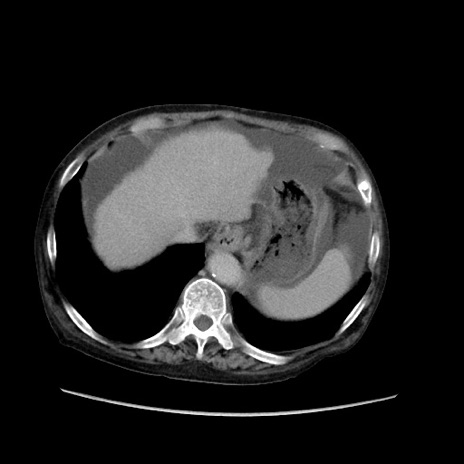

症例31(横断像)

【症例】80歳代 女性

【主訴】腹部膨満感

【現病歴】他院にて肝硬変にてフォロー中。1週間前から便秘、腹部膨満感、臍部腫瘤あり受診となる。

【既往歴】肝硬変

【身体所見】腹部膨隆あり、皮膚変化なし、疼痛なし。

【データ】WBC 4600、CRP 0.25